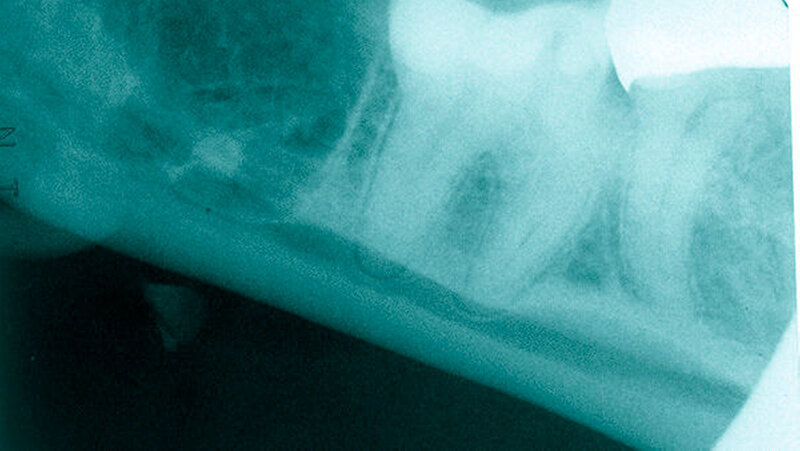

Zur bildgebenden Diagnostik erfolgten ein Orthopantomogramm und alio loco eine Zahnfilmaufnahme, bei der sich der dislozierte Wurzelrest des Zahnes 48 circa 3 mm kaudal der Alveole projizierte. In der durchgeführten digitalen Volumentomografie stellte sich der Wurzelrest kaudal der Linea mylohyoidea und medial der Tuberositas pterygoidea im Bereich der rechten Submandibularloge dar (Abbildungen 1 bis 4). Die operative Entfernung des Wurzelrests erfolgte durch einen transoralen Zugang in nasotrachealer Intubationsnarkose. Als operativen Zugang in den posterolateralen Mundboden beziehungsweise in die Submandibularloge rechts wurde der bestehende gingival geführte Winkelschnitt durch einen lingualen Zahnfleischrandschnitt aus regio 47 bis 43 sowie durch eine transversale Verbindung disto approximal 47 erweitert. Die daraus resultierende H-förmige Schnittführung erlaubte die subperiostale Darstellung des Ramusvorderrands und das retrograde (von der Koronoidkerbe ausgehende) Auslösen des lingualen Weichgewebes zur Bildung eines lingualen Mukoperiostlappens. Nach stumpfer Präparation einer Kavität entlang der lingualen Innenkortikalis und um die konvexe Kontur des retromolaren Knochenbalkons bis auf die Kranialfläche des M. mylohyoideus wurde der Muskel im Dorsalbereich seiner Insertionslinie mit der Schere scharf abgetrennt, um die Submandibularloge von kranial zu eröffnen. Die Retraktion des Mukoperiostlappens nach intermaxillär führte zur übersichtlichen Exposition der gesamten Retromolarregion und der Möglichkeit, unter Schonung des N. lingualis in die Submandibularloge einzugehen (Schnittführung siehe Abbildung 5). Im lingualen Kortex der Alveole regio 48 wurde eine Perforation in den Mundboden von etwa 6 bis 7 mm Durchmesser als Durchtrittsstelle für den Wurzelrest identifiziert (Abbildung 6).